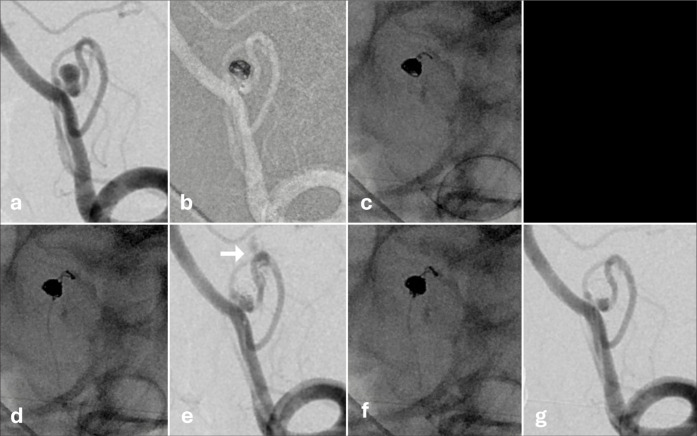

Background: Coil embolization for cerebral aneurysms is an important technique and is not likely to be replaced in the foreseeable future. Recently, the Target Tetra detachable coil (TTDC) has become available, thereby raising expectations for a safer embolization in small aneurysms. Based on our experience, we report the behavioral characteristics and effective utilization of TTDCs.

Methods: We analyzed 28 patients who underwent surgery using the TTDC for intracranial aneurysms between December 2023 and November 2024.

Results: Five cases were treated using the TTDC only. In four of five cases, the aneurysm height was <3 mm. In terms of complications, intraprocedural rupture occurred in two cases and thrombosis in two. None of the patients presented with delayed hemorrhage during the follow-up period.

Conclusion: The TTDC coils cluster at the tip of the microcatheter. Thus, effective embolization can be achieved by filling from the deeper available space. Based on the behavioral characteristics of TTDCs, it is not only beneficial as a finishing coil but also plays a role in filling. We believe that TTDCs may be a useful option for embolizing small aneurysms, including ruptured ones that were previously challenging to treat, and cases in which microcatheter stability are compromised.